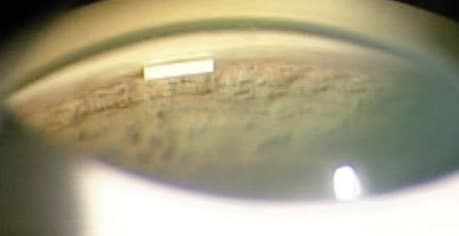

Figure 1. Ocusert, a pilocarpine ophthalmic ocular insert system introduced in the 1970s.

Pilocarpine, the original drug used to treat glaucoma, requires administration 3 to 4 times a day and is associated with side effects including miosis, brow ache, and blurred vision. To mitigate the dosing schedule and reduce symptoms, slow-release versions of this medication began to be offered in the 1970s, such as pilocarpine hydrochloride ophthalmic gel 4% (Pilopine HS, Alcon) and the pilocarpine ophthalmic ocular insert system (Ocusert Pilo, Alza Corp). These did not take hold. Pilocarpine gel could be irritating to the eye and difficult to administer. The ocular insert could also be difficult to place and often fell out. However, these treatments helped to pave the way for subsequent efforts to provide sustainable, consistent drug delivery, including punctal plugs and a bimatoprost-eluting corneal ring.